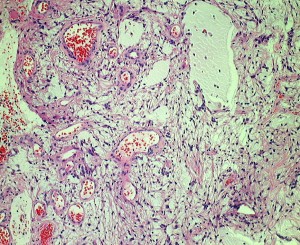

小児期の毛様細胞性星細胞腫

10才小児の小脳結節性毛様細胞性星細胞腫です。典型的な良性腫瘍として知られる毛様細胞性星細胞腫です。

HE染色です。左のように双極性突起を延ばす小型の核を有する充実性部分 compact part と,中央に見られるような細胞間に微小嚢胞変性と類粘液性基質がみられる海綿状部分 spongy partが混在する毛様細胞性星細胞腫に特徴的なbiphasic patternがみられます。右側の画像では小さな粘液基質を含みながらびまん性星細胞腫に類似する組織像が認められます。左の画像の矢印で示す赤い玉のようなものはeosinophilic granular bodiesです。

左がS100,中央がGFAP,右がMIB-1 (Ki-67)染色です。MIBはやや高値で3%と報告されました。病理組織診断は,WHO grade 1 毛様細胞性星細胞腫です。